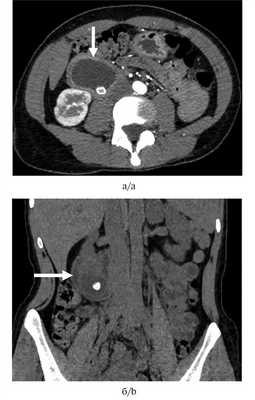

Выполнена КТ органов брюшной полости, по переднелатеральной поверхности общего желчного протока обнаружено кистозное образование размером 52×60×35 мм, в просвете которого имелся конкремент размером 10 мм. Просвет ДПК на этом уровне сужен (от нитевидного до 5 мм) (рис. 1).

Рис. 1. Компъютерная томограмма органов брюшной полости.

а — аксиальная проекция, артериальный фаза — дупликационная киста двенадцатиперстной кишки с конкрементом в просвете; б — фронтальная проекция, нативная фаза, стрелкой указан суженный просвет двенадцатиперстной кишки.